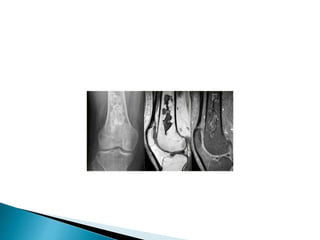

 2nd mostcommon primary bone tumor and highly malignant.  50% around the knee.  Presentation: pain, mass, pathologic fracture.  Sclerosis is present from either tumor new bone formation or reactive sclerosis.  Age: most commonly seen in 10-25 years, but may occur in older patients.

 Plain filmstypically reveal lesions with moth- eaten or permeative pattern of the transition zone with irregular cortical destruction and an interrupted periosteal reaction with soft tissue extension. .

 A periostealreaction known as Codman's triangle appears as tumor elevates periosteum from underlying bone.  Cortical soft tissue extension may produce radiating spicules of bone called sunray appearance